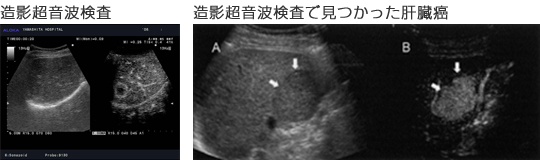

造影超音波検査は、卵アレルギーの患者さん以外で、CTやMRI 等の検査で造影剤を使うことが出来なかったアレルギーの方や、腎臓の働きが悪い方にも安全に行える検査法です。